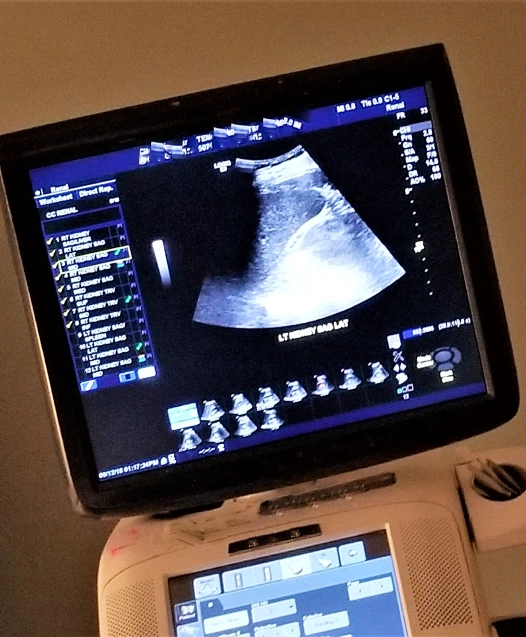

Ultrasound imaging is an essential diagnostic tool that allows veterinarians to evaluate your dog’s internal organs and soft tissues without invasive surgery. It’s a non-invasive procedure that provides real-time images of the body’s internal systems, helping the vet diagnose health issues quickly and with precision.

- Kidney and Liver Function: Highly effective at evaluating kidney and liver health. It can detect early signs of disease, such as organ enlargement, cysts, or abnormal masses. Early detection can significantly improve treatment success.

- Real-time Imaging: The ability to view internal organs in real time enables dynamic observations, helping make quicker, more accurate treatment decisions.

- High Diagnostic Precision: Ultrasound provides clear, detailed images that improve diagnostic accuracy, enabling better-targeted treatments and monitoring disease progression or recovery.